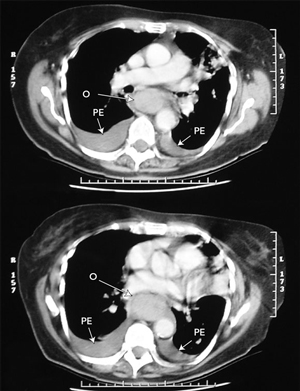

Dissecting haematoma of the oesophagus has a typical appearance on imaging.4,5 Barium swallow shows a long, smooth tubular filling defect in the lumen of the oesophagus, sometimes with the dissection space filled with a stripe of contrast (the “double-barrelled oesophagus”). As the dissection most commonly occurs along the posterior wall, the lateral view is most useful. Computed tomography demonstrates an obliterated lumen with thickening of the wall. This extends over a long length of the oesophagus, and can mimic oesophageal rupture or extensive malignancy. The haematoma is large, fluctuant, and blue or purplish when viewed at endoscopy. Delayed endoscopy shows a long ulcer, where the overlying mucosa has sloughed, followed by rapid regeneration and an ultimately normal appearance.3